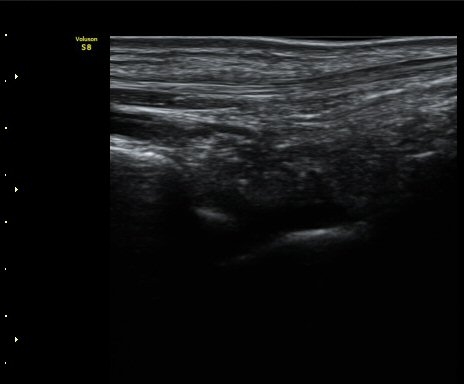

Àü°Å°ñºñ°ñÀδë Á¾´Ü¸é°Ë»ç»ó Àδë ÀδëÀÇ Àú¿¡ÄÚ ºÎÁ¾°ú(±×¸² 3)

ºñ°ñºÎÂøºÎ ¿¬°á¼º ¼Ò½ÇÀÌ °üÂûµÈ´Ù(±×¸² 4).

±×¸²3) Àü°Å°ñºñ°ñÀδë Á¾´Ü¸é°Ë»ç

±×¸²4) Àü°Å°ñºñ°ñÀδë Á¾´Ü¸é°Ë»ç